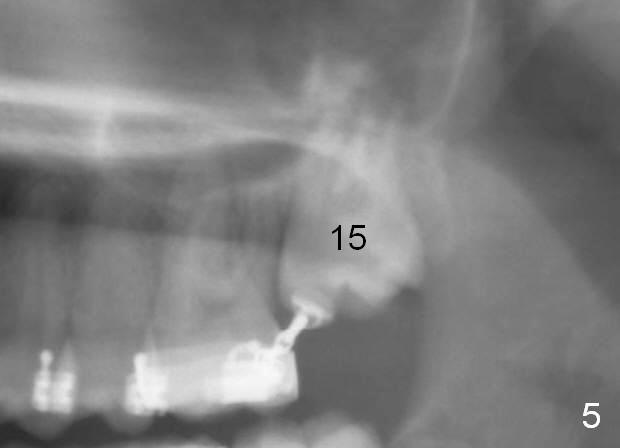

When the female patient was 11 years 2 months (Fig.1) and 12 years 10 months (Fig.2) old, the eruption of #15 is delayed. The tooth is surgically uncovered with bonding an eruption chain 1 month post banding. Three (Fig.3), 4 (Fig.4) and 6 (Fig.5) months post banding, eruption appears to be slow with elastics.

The distobuccal cusp of the tooth is subgingival 8 months post banding (Fig.6 (mirror view) *). A 2nd surgery is performed to expose the gold chain (Fig.7 <) and a bracket is placed. With arch wires, eruption of the impacted tooth is quickened (Fig.8). Later a 3rd minor surgery is done to place a lingual button to facilitate lingual cusp eruption. Finally a band has to be placed at #15. Treatment finishes in 2 years. The patient (15 years 2 months old) returns for follow up 3 months post debanding (Fig.9). There is no bone loss around the tooth #15 2 years 4 months post de-banding (Fig.11, as compared to the tooth #2 (Fig.10)).